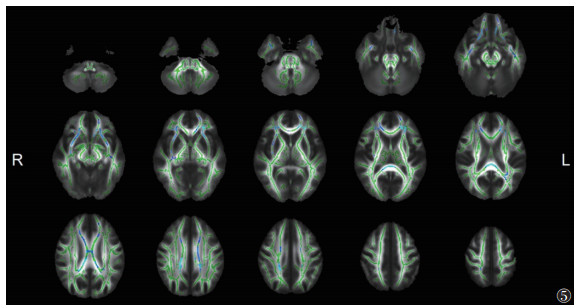

与EMTB组相比,ITB组脑白质显示出较广泛的FA降低和MD升高(P<0.05,TFCE和FWE校正)(图 5,6),其范围小于ITB组与HC组之间的差异。其中胼胝体膝部、双侧前放射冠等同时出现FA降低和MD升高(图 7)。

![]() |

| 注:与EMTB组相比,ITB组脑白质FA降低的区域显示为蓝色(P<0.05,TFCE和FWE校正)。脑白质骨架显示为绿色。L,左;R,右 图 5 ITB组与EMTB组FA的差异 |